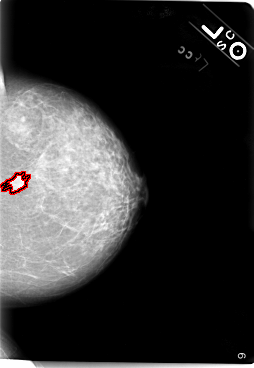

B_3017_1.LEFT_MLO

LEFT_MLO LINES 5848 PIXELS_PER_LINE 4040 BITS_PER_PIXEL 12 RESOLUTION 50 OVERLAY

FILE: B_3017_1.LEFT_MLO.OVERLAY

TOTAL_ABNORMALITIES 1

ABNORMALITY 1

LESION_TYPE MASS SHAPE LOBULATED MARGINS ILL_DEFINED

ASSESSMENT 4

SUBTLETY 4

PATHOLOGY MALIGNANT

TOTAL_OUTLINES 1

BOUNDARY